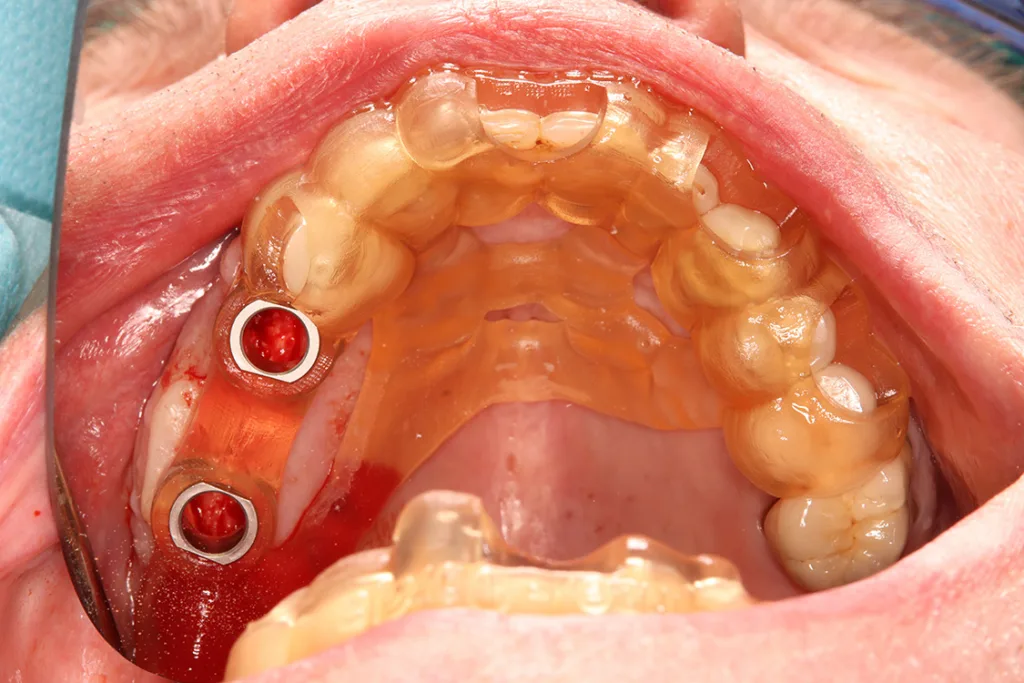

Indikation: Herausnehmbarer Zahnersatz

Die additive Fertigung von herausnehmbarem Zahnersatz ist bereits im Bereich der SLM-Technologie für Modellgussprothesen und Teleskopprothesen weit verbreitet [17] (Abb. 9). Mittlerweile können Prothesenbasen oder die Ersatzzähne von Prothesen für Modellgüsse, Teleskopprothesen, aber auch für Vollprothesen gedruckt werden. Für die additive Fertigung von Totalprothesen kommen derzeit vor allem das DLP-Verfahren sowie das Material Jetting zum Einsatz, die eine sehr kosteneffiziente Lösung im Vergleich zu herkömmlichen Fertigungstechnologien bieten. Dennoch ist in diesem Fall zu beachten, dass die gedruckten Prothesenbasen für permanente Prothesen in ihrer Passungsgenauigkeit und Oberflächengenauigkeit schlechter abschneiden als gefräste Prothesen. Auch hier sind die Weiterentwicklung und Langzeitdaten abzuwarten.